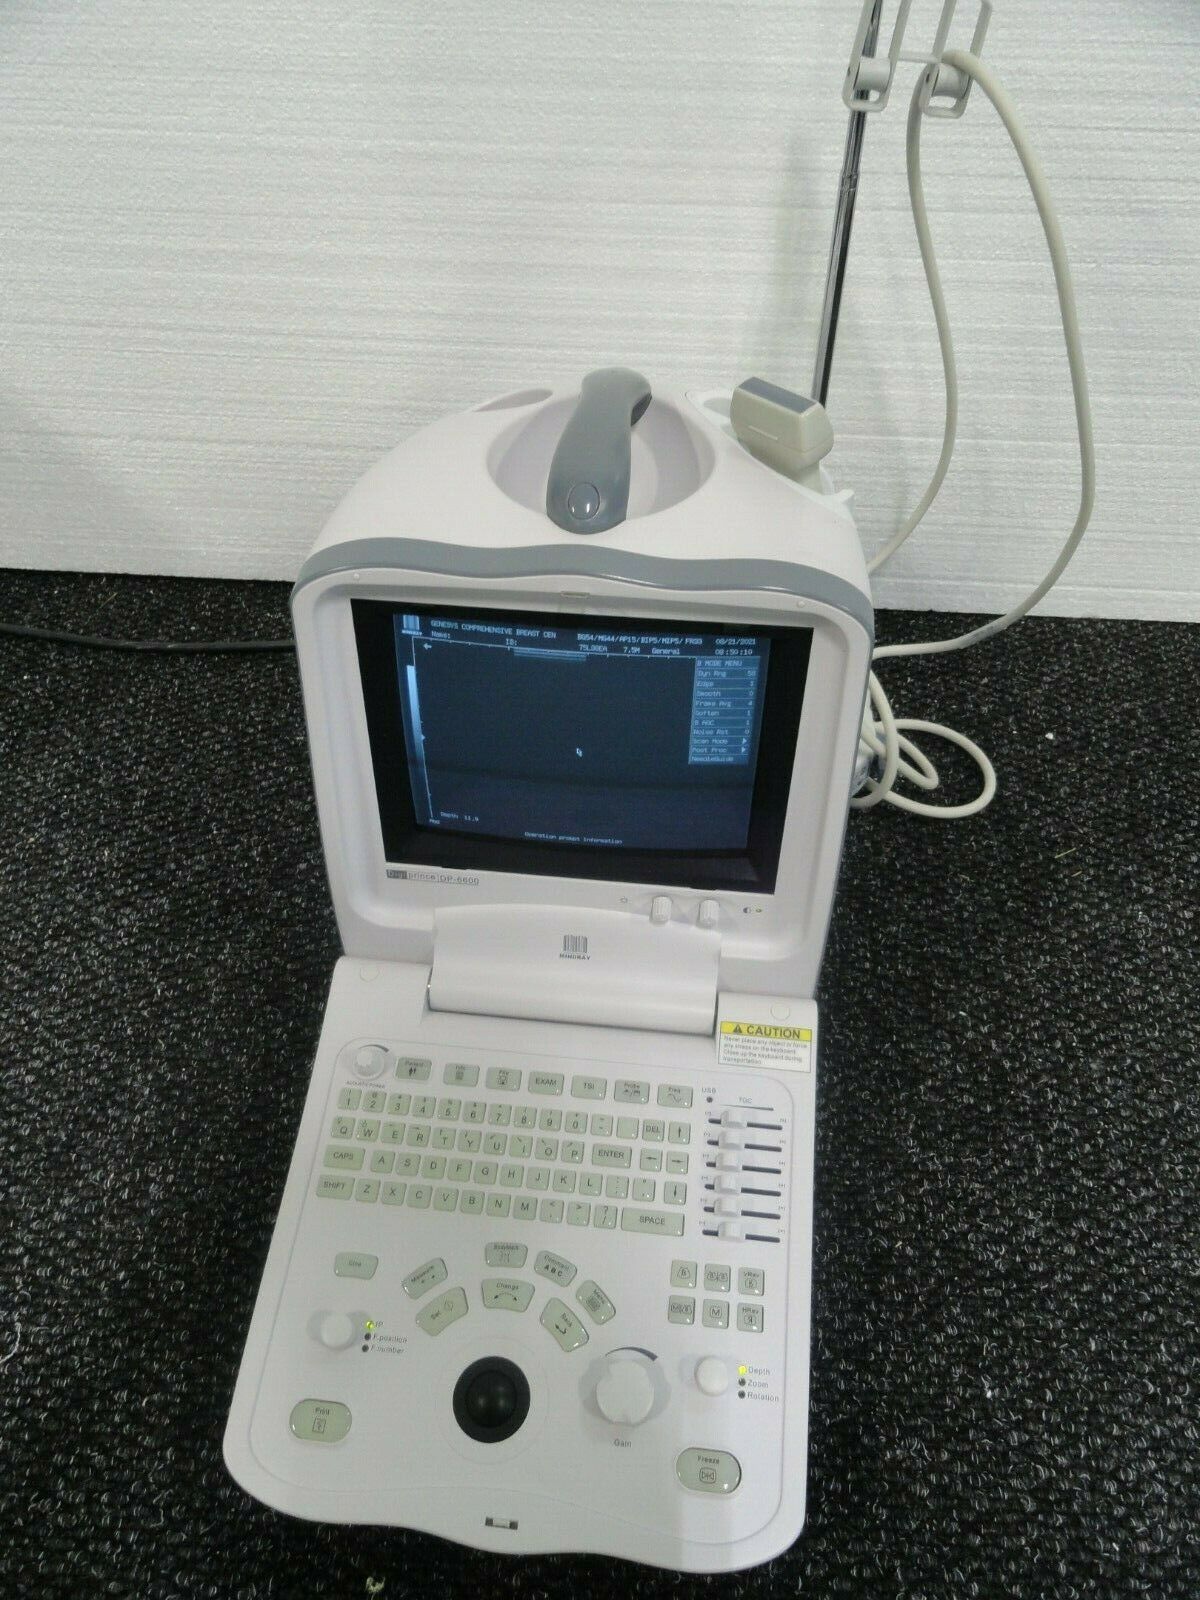

Mindray DigiPrince DP-6600 Ultrasound Machine with Transducer

Sale price$ 10,492.00

Regular price$ 11,192.00

Save $ 350.00

Mindray DP-6600 Digital Portable Ultrasound with Linear Probe Transducer

Sale price$ 2,550.00

Regular price$ 2,720.00

MINDRAY DP-6600 ULTRASOUND SYSTEM + 2 TRANSDUCER

Sale price$ 8,628.99

Save $ 550.00